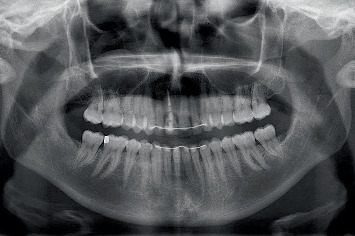

简介:当用种植体替换美学区单个牙齿时,对于大面积颊骨缺损的病例,保留牙槽嵴是必要的。假体驱动种植体放置在保留的脊上,随后立即进行患者特定的临时修复,可以通过数字治疗计划实现。数字化工作流程结合了口腔内光学扫描和锥形束计算机断层扫描,实现了三维临床和放射学解剖评估。此外,它通过计算机辅助手术和CAD/CAM钛基台的临时修复预制,促进了完全引导的种植体放置。材料与方法:对3例上颌美观区缺牙及颊骨缺损bbbb5 mm的患者行牙槽嵴保存术。四个月后,使用数字工作流程放置种植体,并使用患者特定的钛基台进行预制临时修复。3个月后进行了最终修复。在治疗前、临时修复后6周、最终修复后1个月和1年评估临床、美学、放射学和患者报告的结果。结果:3例患者在牙槽嵴保存后伤口愈合良好,种植体可按计划放置并临时修复。在最后的随访中,观察到健康的种植体周围组织,美观性好,患者满意度高。结论:三个报告的病例展示了数字工作流程在上颌美学区保留脊中使用预制修复体进行延迟种植体放置的潜力。

Introduction: When replacing a single tooth in the aesthetic zone with an implant, alveolar ridge preservation is necessary in cases with extensive buccal bone defects. Prosthetically driven implant placement in the preserved ridge, followed by an immediate patient-specific temporary restoration, can be achieved with digital treatment planning. A digital workflow incorporates intraoral optical scanning and cone beam computed tomography, enabling a three-dimensional clinical and radiographic anatomy assessment. Furthermore, it facilitates fully guided implant placement by means of computer-assisted surgery and the prefabrication of temporary restorations with a CAD/CAM titanium abutment. Materials and Methods: Three patients with a failing tooth in the maxillary aesthetic zone and a buccal bone defect > 5 mm underwent alveolar ridge preservation. Four months later, a digital workflow was used to place the implant, which was restored with a prefabricated temporary restoration with a patient-specific titanium abutment. The definitive restoration was placed 3 months later. Clinical, aesthetic, radiographic, and patient-reported outcomes were assessed before treatment, 6 weeks after temporary restoration, and 1 month and 1 year following definitive restoration. Results: In all three cases, wound healing after alveolar ridge preservation was uneventful, and the implants could be placed and restored with a temporary restoration, as planned. At the final follow-up, healthy peri-implant tissues were observed with good aesthetics and high patient satisfaction. Conclusion: The three reported cases demonstrate the potential of a digital workflow for delayed implant placement with provisionalization using prefabricated restorations in preserved ridges within the maxillary aesthetic zone.